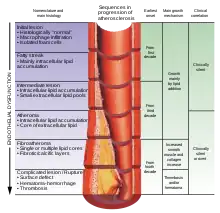

Hypertension and atherosclerosis are risk factors for both atherosclerotic plaques and thromboembolism. In atherosclerotic formations, a plaque develops under a fibrous cap. When the fibrous cap is degraded by metalloproteinases released from macrophages or by intravascular shear force from blood flow, subendothelial thrombogenic material (extracellular matrix) is exposed to circulating platelets and thrombus formation occurs on the vessel wall occluding blood flow. Occasionally, the plaque may rupture and form an embolus which travels with the blood-flow downstream to where the vessel narrows and eventually clogs the vessel lumen.

- Heart: Myocardial infarction (MI), commonly known as a heart attack, is an infarction of the heart, causing some heart cells to die. This is most commonly due to occlusion (blockage) of a coronary artery following the rupture of a vulnerable atherosclerotic plaque, which is an unstable collection of lipids (fatty acids) and white blood cells (especially macrophages) in the wall of an artery. The resulting ischemia (restriction in blood supply) and oxygen shortage, if left untreated for a sufficient period of time, can cause damage or kill heart muscle tissue (myocardium).